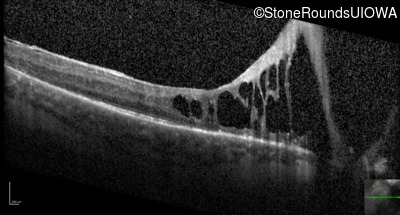

Optical Coherence Tomography - Right - Hand Motion

Exemplar / OCT Stack

OCT Stack

Optical Coherence Tomography - Left - 20/600 sc